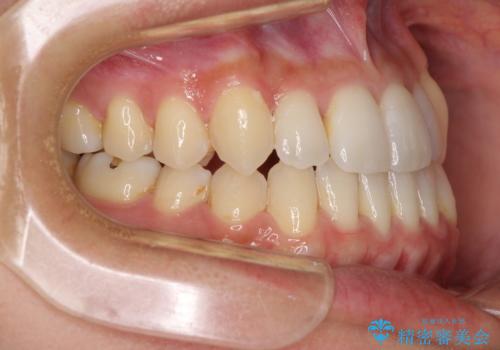

前歯のデコボコ インビザラインによる矯正治療

- 上下前歯の叢生と奥歯の反対咬合を気にして来院された患者様です。

インビザラインを用い、下顎はIPR(歯と歯の間を削る)と歯列全体を後方に移動させ、上顎は側方に拡大させることで歯列を改善していくこととしました。

骨格的に下顎が左側前方にずれているため、上下正中のズレや左右奥歯の咬み合わせを理想的な状態とすることは困難でした。